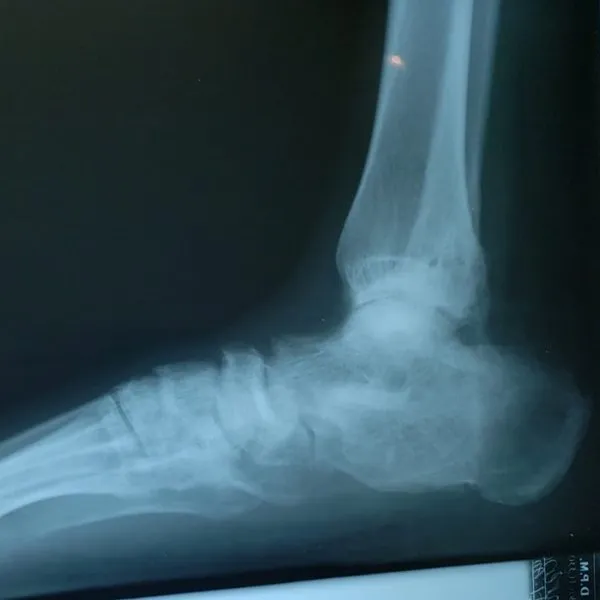

Sports Medicine and Trauma

Whether you've suffered a foot injury at work or competing in a sport, we'll provide professional care to you get back on your feet again sooner.

Foot and Ankle Care

Our clinic treats a wide range of foot conditions from corns to heel spurs. Walk-ins are welcome and same-day appointments are available!

- X-rays